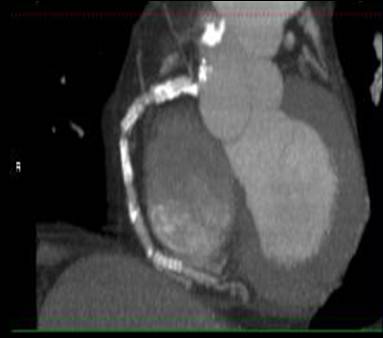

The non-invasive imaging modality of multi-detector computed tomography has dramatically evolved the last ten years and that is due to hardware and software developments. The newer generation of scanners allows increased spatial and temporal resolution that improves the clinical reliability giving further insights into the evaluation of coronary artery disease. Heart morphology imaging followed by studies of myocardial function and assessment of cardiac valves can be performed from the information derived from the data of the coronary artery examination. Also, the venous anatomy of the heart, coronary artery bypass grafts, stents, and cardiac tumors can be imaged and evaluated when necessary. For the beneficial use of this method, entrance criteria for different patient groups need to be set in order to allow improved outcome of multi-detector CT.